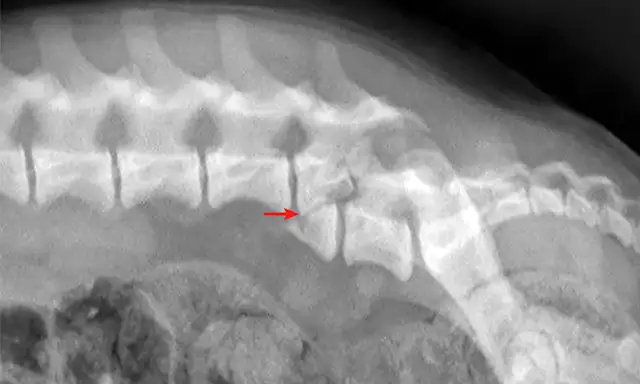

Figure 1

Lateral radiograph of a dog following unknown trauma. There is a complete oblique fracture (arrow) of the L6 vertebral body and luxation of the L6-L7 articular processes, with severe cranioventral displacement of the caudal segment. Despite the degree of displacement, this patient retained voluntary movement in both pelvic limbs on initial examination and made a functional recovery following reduction and stabilization of the fracture/luxation and 8 weeks of crate confinement.